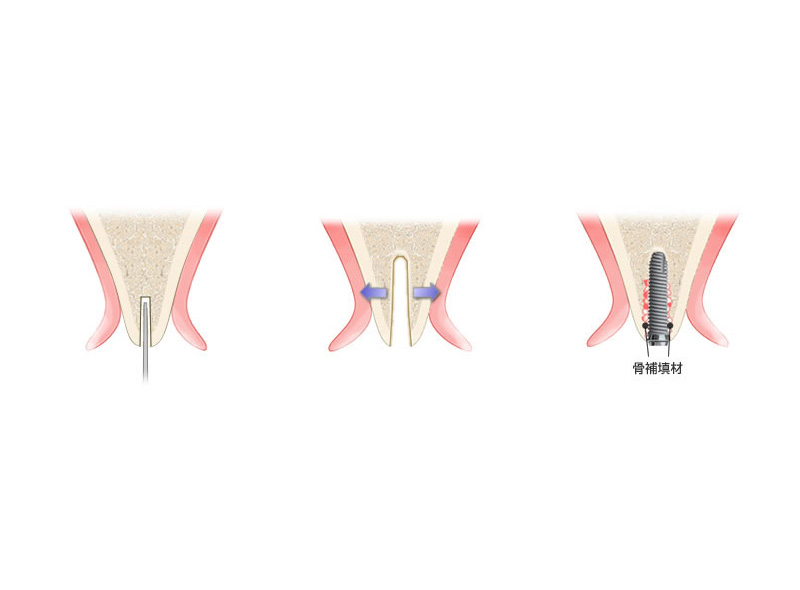

スプリットクレスト法

~骨が少なくてインプラントは無理といわれた患者さんへ

インプラント手術において一番頻繁に問題となることはインプラントを埋入するのに十分な骨量がないことです。とくに前歯は骨の高さには問題ないですが、幅が不足してることがおおいです。このようなとき骨の頂上部にクサビのような形の特殊な器具を挿入しながら、少しずつ骨幅を広げインプラントの埋入が可能な状態にします。

メリット

- 骨を削る量を最小限に抑えるため、患者さんの身体的な負担を軽減できます

- 骨の幅が3mm程度の症例でも、骨を分割・拡張してインプラントの埋入を可能にします

- 従来法では対応が難しかった、薄い骨の症例にも適用できる可能性があります

デメリット

- 保険対象外となり治療費が高額になる可能性があります

- 骨質が硬い下顎や、隣接歯がある部位など、適用が難しい場合があります

- 骨を正確に分割・制御するには、術者の高度な技術が不可欠です

- 稀に術後の骨吸収が起こる可能性があります